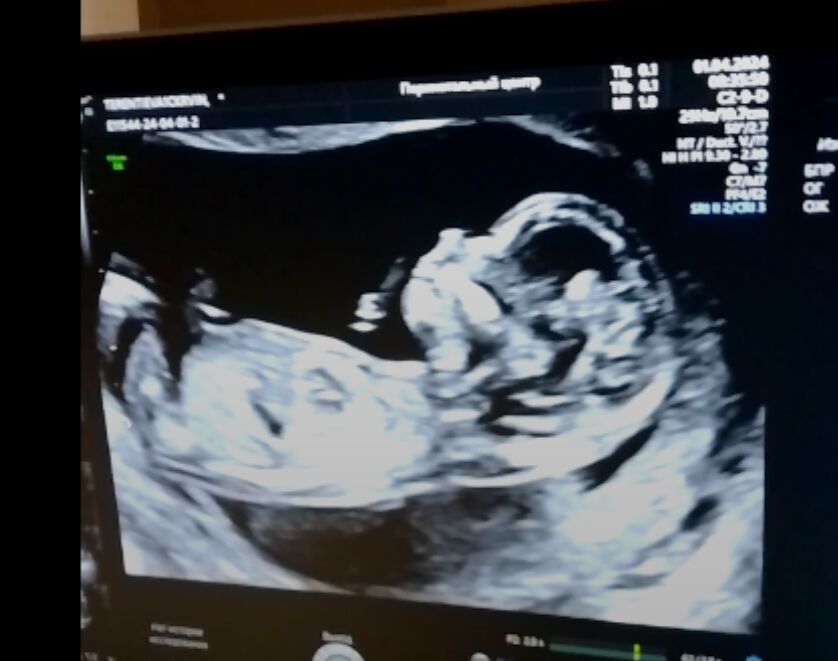

1 апреля 😁 день дурака ,а мне с утра не до смеха было ,а было очень волнительно,так как был первый и он же самый важный скрининг ❤️ какое счастье видеть в заключении просто срок беременности,без каких либо пометок 🙏🏼 всё замечательно!срок даже не 13 недель поставили,а 13+3))подтвердили нам нашу девочку 😁ждём Дарью Олеговну ❤️пдр 4 октября,у меня др 6 октября,у Миры (младшая дочь)12 октября 😁 Октябрята ❤️🍂🍁☘️